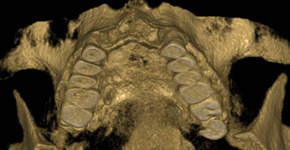

Je speciální zubní digitální tříprostorový tomograf (3D), který umožňuje na základě jediného

snímkování vytvořit všechny typy RTG zobrazení, které jsou pro lékaře potřebné. Díky používané technologii tzv. „kuželového paprsku“ a speciálním senzorům je

výrazně zmenšená dávka záření - o více jak 80% proti klasickému CT vyšetření. To je významné zejména u dětí. Pomocí tohoto přístroje je možné zjisti skutečnou situaci v čelistních kostech pacienta tedy množství kosti - můžeme změřit skutečnou šířku i výšku kosti, i kvalitu kosti (hustotu) v místě uvažované implantace. 3D (tříprostorové) zobrazení umožňuje zvýšit prostorovou představu operatéra ještě před vlastní operací a zároveň pacientovi lépe objasnit a ukázat oblast plánovaného zavedení implantátu.

Pacient „neumí číst“ RTG snímky, ale díky 3D zobrazení vidí „svoji skutečnou čelist“

- např. jak je nízká či úzká, vidí průběh nervu nebo velikost čelistní dutiny, což mu umožní i pochopení nutnosti v některých případech provést pomocné zákroky ještě před vlastním zavedením implantátu (viz. kostní štěp, sinus lift, kostní granulát...).

Vyšetření pomocí tohoto přístroje používáme i ve stomatochirurgii (zlomeniny čelistí, zuby moudrosti, cysty, onemocnění čelistního kloubu), ortodoncii (retinované zuby, nadpočetné zuby), parodontologii atd.